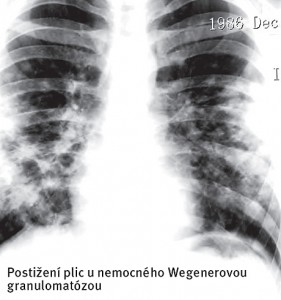

Wegenerova Granulomatóza (WG) je chronická systémová vaskulitida postihující malé a střední cévy hlavně v oblasti horních (nos a vedlejší nosní dutiny) a dolních (plíce) dýchacích cest a ledvin. Pojem „granulomatózní“ se vztahuje k mikroskopickému vzhledu postižené tkáně, ve které jsou v okolí cév patrna uzlíkovitá ložiska.

U velké části pacientů nemoc začíná protrahovanými projevy zánětu vedlejších nosních dutin, které neustupuje po antibioticích. Na nosní přepážce se tvoří strupy (krusty), může docházet k opakovanému krvácení z nosu i tvorbě vředů, které vedou k následnému zborcení nosní přepážky a vzniku tzv. sedlovitého nosu. Zánět v dýchacích cestách může způsobit chrapot a dýchací potíže. Zánětlivé uzlíky v plicích mohou působit dojmem zápalu plic s kašlem, dušností a bolestmi na hrudi.

V roce 1990 ACR vypracovala klasifikační kritéria Wegenerovy granulomatózy. Tato kritéria jsou: 1.- zánět nosní nebo ústní sliznice, charakterizovaný vznikem vředu nebo hnisavým či krvavým výpotkem z nosu, 2.- přítomnost abnormalit na RTG hrudníku: uzly, fixní okrouhlé infiltráty nebo dutiny, 3.- glomerulární mikroskopická hematurie nebo nález erytrocytárních válců v sedimentu vyšetření moči, 4.- granulomatózní zánět intra-, peri- či extravaskulárně, prokázaný biopticky (biopsií ledvin).

2.- přítomnost abnormalit na RTG hrudníku: uzly, fixní okrouhlé infiltráty nebo dutiny,